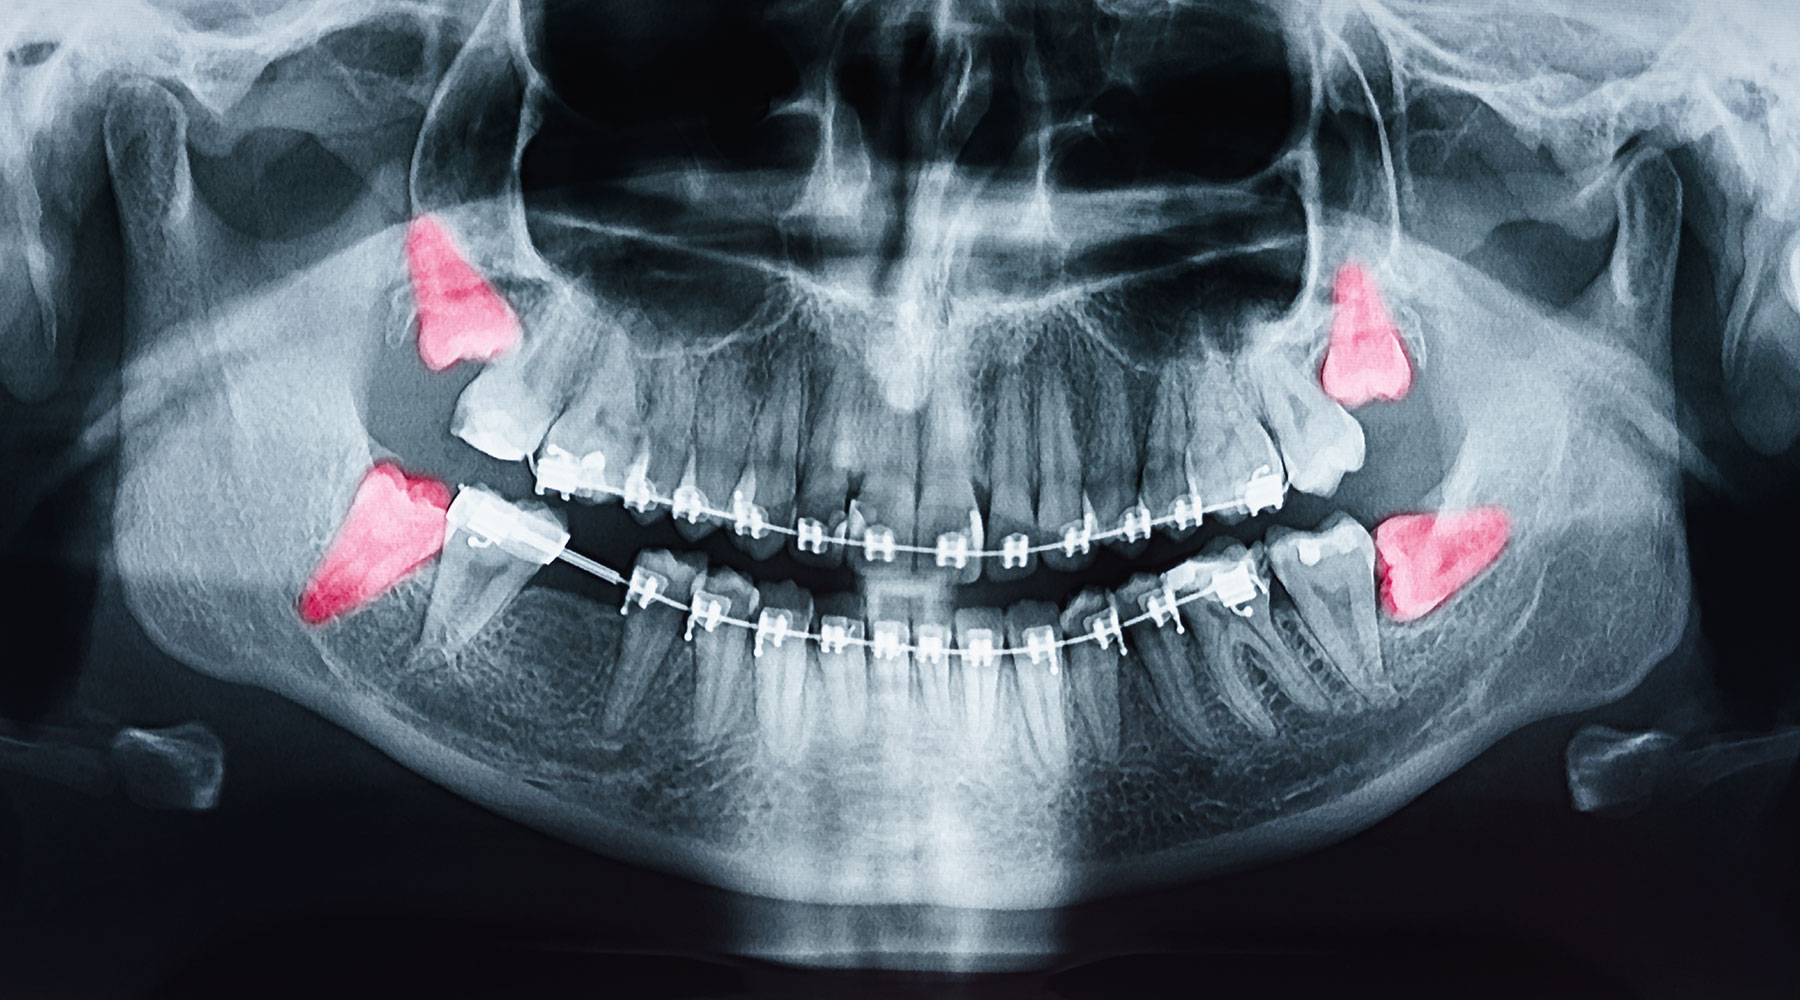

Folgende Grafik zeigt, wie ein Gebiss mit Weisheitszähnen aussehen kann.

- Wenn Sie das Gefühl haben, dass Ihre Weisheitszähne kommen, empfiehlt sich ein Besuch beim Zahnarzt. Dieser kann mit Hilfe einer Röntgenaufnahme entscheiden, ob sie im Gebiss bleiben können oder ob sie gezogen werden sollten.